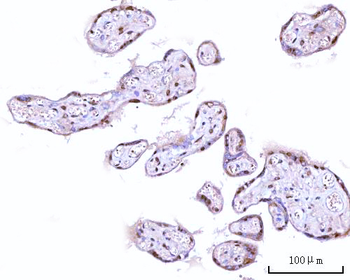

IHC staining of FFPE human lymph node with CD72 antibody (clone BU40). HIER: boil tissue sections in pH9 10mM Tris with 1mM EDTA for 20 min and allow to cool before testing.

IHC staining of FFPE human lymph node with CD72 antibody (clone BU40). HIER: boil tissue sections in pH9 10mM Tris with 1mM EDTA for 20 min and allow to cool before testing.